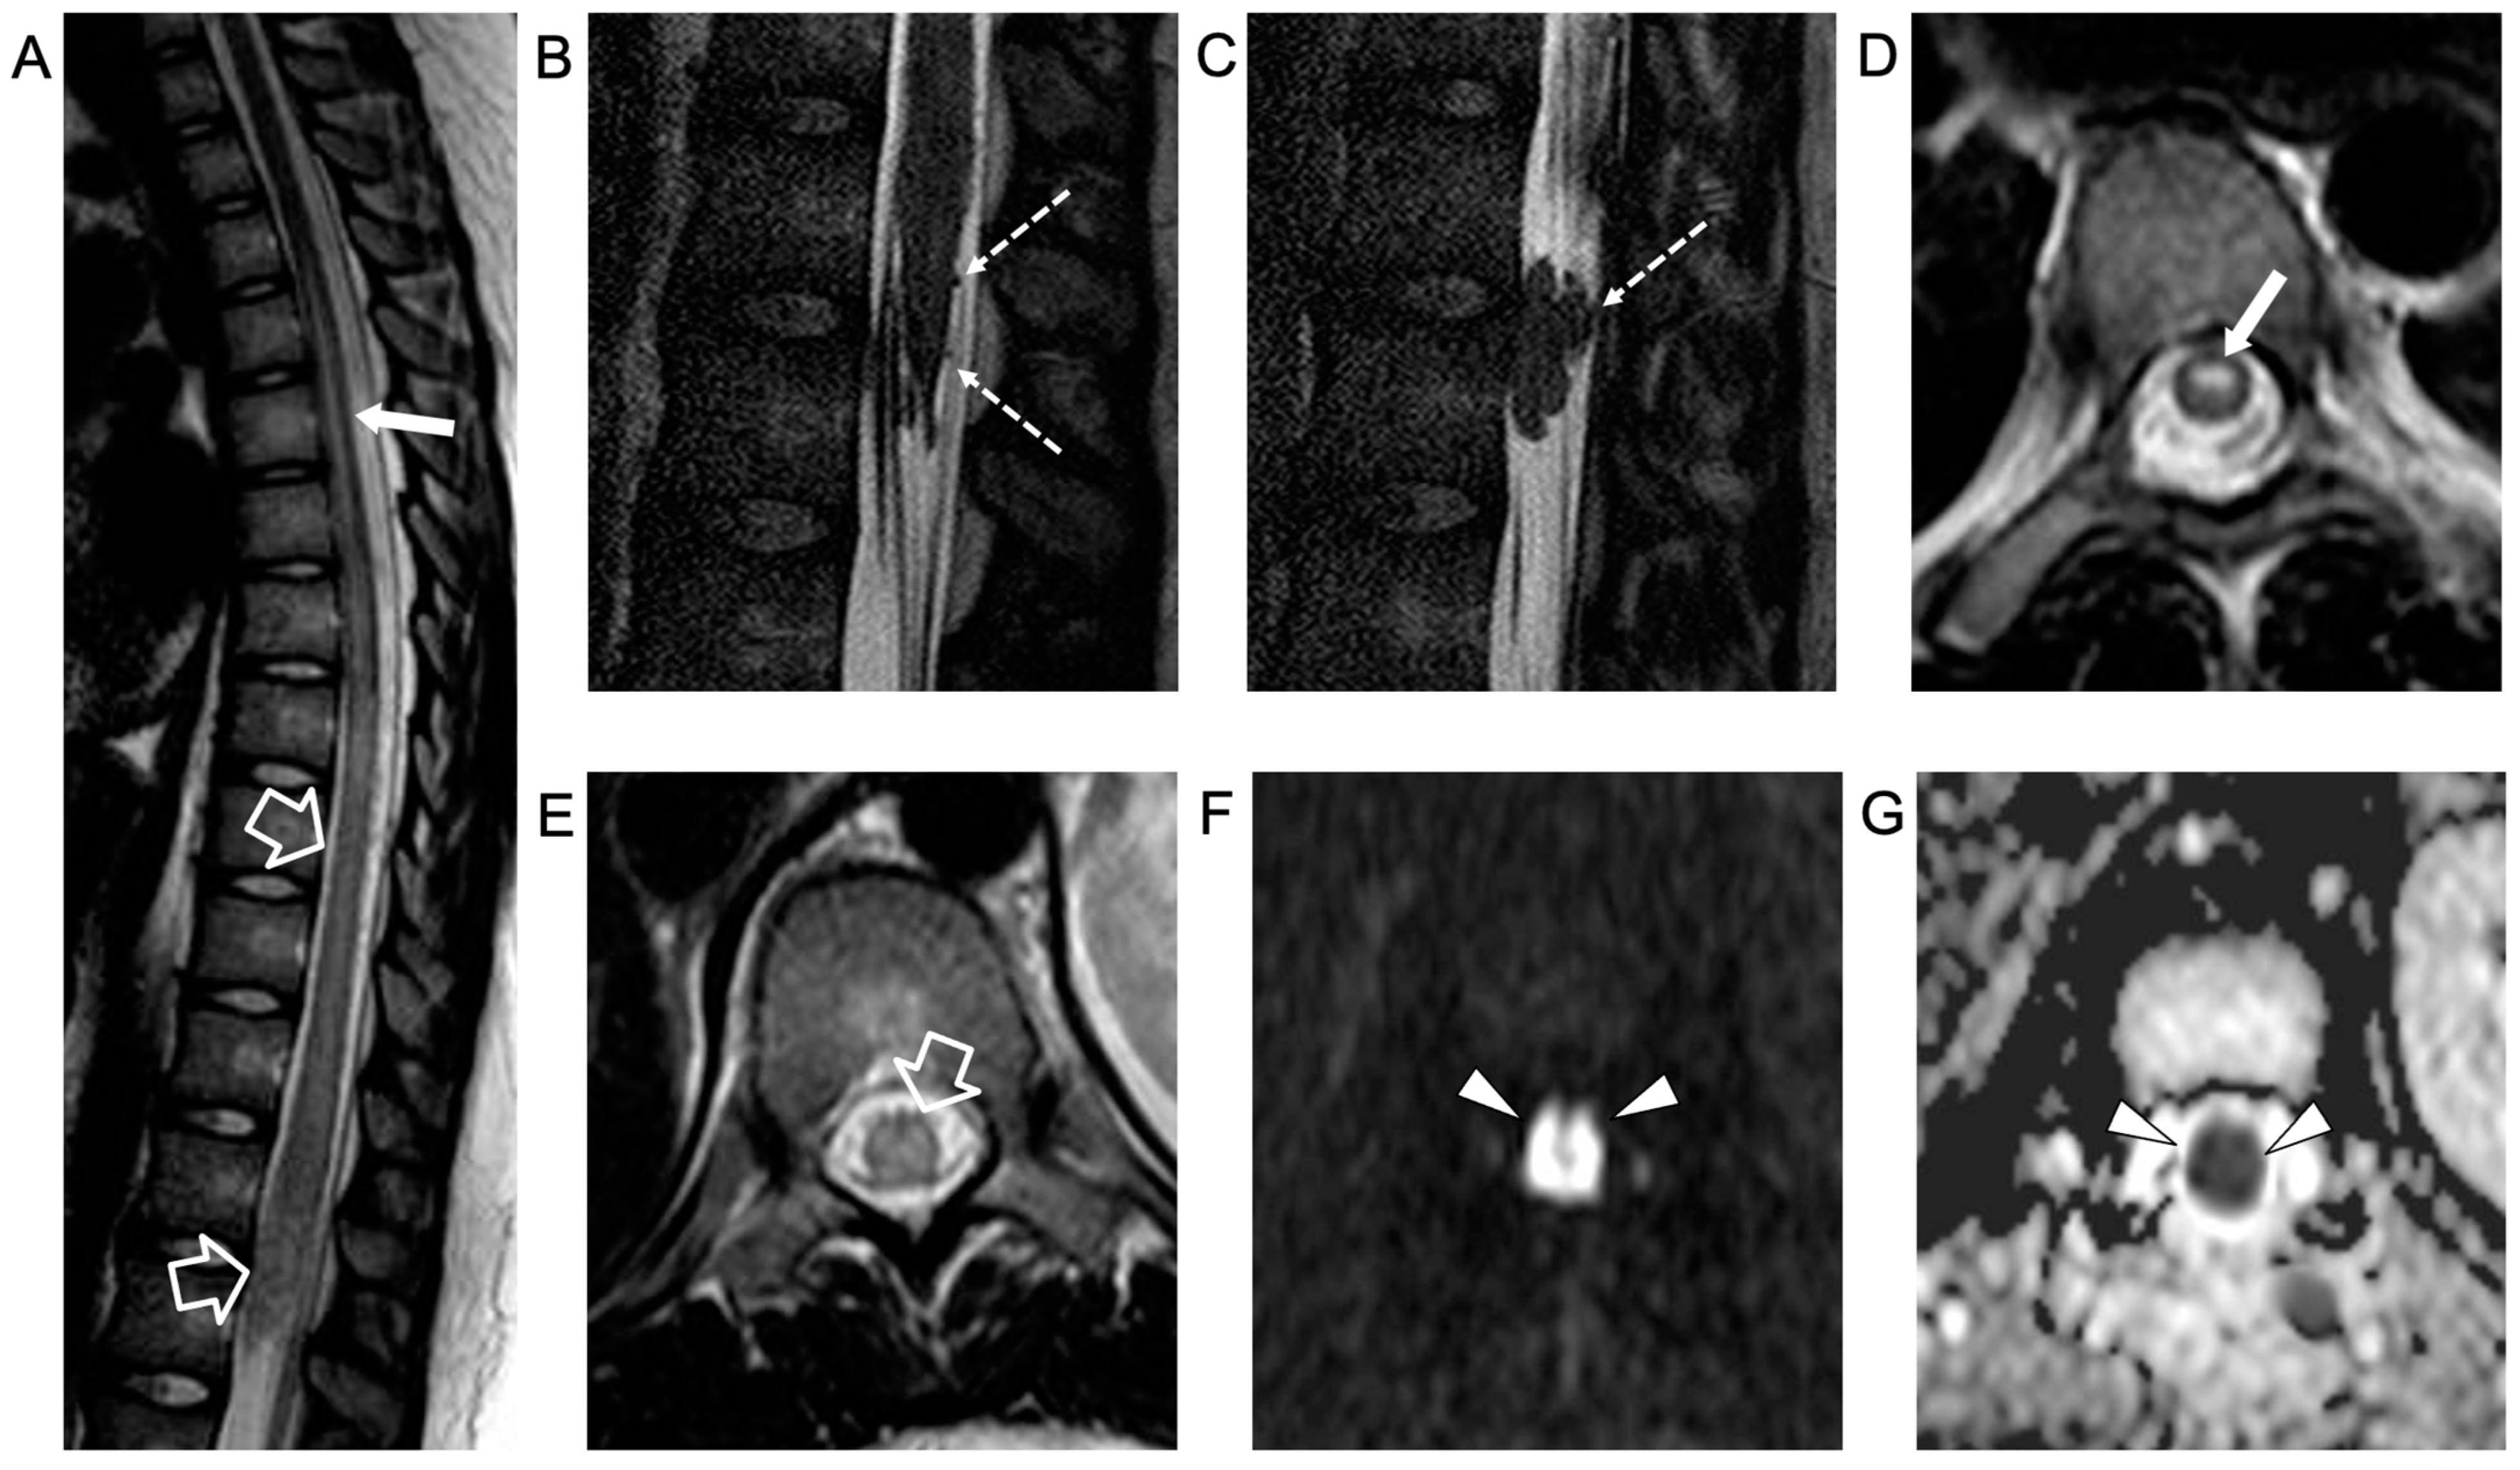

In the following months, repeated MRI studies revealed progressive disappearance of the intradural extramedullary lesions, regression of cauda equina contrast enhancement, and chronic evolution of the spinal cord lesions. At the last follow-up, performed at 18 years of age, the neurological examination was unchanged, showing complete paralysis of the lower limbs. Spinal MRI revealed stable atrophy and gliotic changes of the affected dorsal spinal cord and conus medullaris (Figure 4).

Figure 4.

Contrast-enhanced spinal MRI performed at the last follow-up, several months after clinical onset. Sagittal T2-weighted (A) and 3D driven equilibrium (DRIVE) (B) images reveal a focal area of mild spinal cord thinning at the superior dorsal level (empty arrow) and an extended segment of severe spinal cord atrophy in the inferior dorsal spinal level (arrowheads).